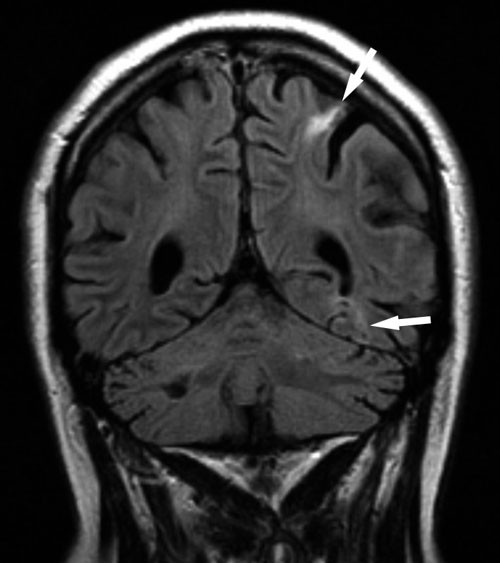

Ved kontroll et halvt år senere hadde det ikke vært akutte episoder med subjektive symptomer, og pasienten anga å være i langsom bedring. Imidlertid gjorde vi enkelte overraskende funn. Ved undersøkelse fant vi betydelig nedsatt tempo i høyre hånd. Dette var ikke beskrevet tidligere. MR cerebrum avdekket flere nye små iskemiske lesjoner i venstre hemisfære (fig 3). Denne gangen var det ingen forandringer i aktuelle arterier som kunne forklare infarktene.